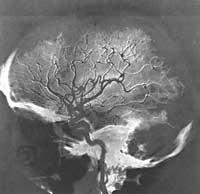

Los estudios volvieron a la nicotina. En 1980 Avram Goldstein y sus compañeros demostraron en la Universidad Stanford de California que el nico tina se asocia estrechamente a determinadas células nerviosas del cerebro de las ratas. Estudios posteriores realizados en numerosos laboratorios han clarificado la distribución de estos puntos de unión en las distintas áreas del cerebro. Algo importante es que esta distribución es prácticamente la misma que la de los receptores para el neurotransmisor acetilcolina. Pero ¿estas zonas de unión afectan a la adicción de la nicotina?

También se han realizado otros experimentos para determinar si la nicotina afecta a las áreas en las que hay muchos puntos de unión en el cerebro. Los miembros del Instituto de Psiquiatría y yo mismo hemos descubierto que las ratas se vuelven más activas –respuesta a la nicotina– inyectando directamente la droga a las áreas celulares que liberan la dopamina neurotransmisora. A este área del cerebro se le denomina sistema de dopamina mesolínico.

Paul Clark, de la Universidad British Columbia de Vancouver (Canadá), ha demostrado que dañando estas células dopaminadas (inyectando neurotoxina selectora) la respuesta a la nicotina disminuye. Además, George Singer de la Universidad de La Trobe en Bundoora (Australia) ha demostrado que lesiones similares reducen la tendencia de las ratas a tomar nicotina. Su influencia en el sistema de dopamina cerebral parece jugar un papel importante en la génesis de los efectos de nicotina que buscan los fumadores.

Este es un descubrimiento muy importante en sí mismo, ya que el sistema de dopamina mesolínico juega un papel importante en la influencia que otras drogas adictivas como las anfetaminas y la cocaína tienen en el momento de reforzar el comportamiento. Es posible que la nicotina fomente también cambios adaptativos en el sistema de dopamina mesolínico (de forma que contribuya a combatir el stress).

Los estudios bioquímicos mantienen la anterior conclusión, demostrando que los terminales nerviosos del sistema de dopamina mesolínico llevan receptores nicotínicos. Peter Rowell y sus compañeros de la Universidad de Louisville en Kentucky han demostrado que pequeñas concentraciones de nicotina, como las que se encuentran en la sangre de los cigarrillos, pueden provocar la liberación de dopamina del sistema mesolínbico. Estas células nerviosas siguen reaccionando con la nicotina a pesar de tomar muchas dosis y no generan tolerancia. Esto sugiere que la liberación de dopamina puede ser importante para el efecto potenciador de la nicotina.

La nicotina, por tanto, puede afectar primero a los receptores de acetilcolina y estos pueden posteriormente activar el sistema de dopamina. La nicotina también puede influir sobre otros neurotransmisores y hormonas (noradrenalina, narcóticos endógenos y prolactina) y provocar la liberación de acetilcolina. Pero hasta ahora estos efectos no parecen darse con las dosis de nicotina de los fumadores, o al menos no se han relacionado directamente con los comportamientos adictivos.

La pregunta a plantear es ¿El efecto de la nicotina en el punto de unión puede explicar todas las consecuencias adictivas y comportamentales? Quizá la respuesta más razonable que podemos dar en la actualidad es decir no. La participación de la dopamina (implicada en otras adicciones y comportamientos premiados) explica sólo parcialmente el efecto de fortalecimiento de la nicotina. También es posible que otro neurotransmisor, el 5-hidroxitriptamina, actúe sobre los receptores 5-HT3 para reforzar el efecto de la nicotina en el sistema dopamina. Además, estudios recientes a nivel molecular indican que entre los principales receptores nicotínicos existen varios tipos con diferencias muy pequeñas.